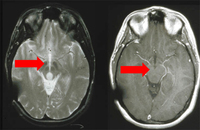

Fratura do osso temporal.

Do acervo de aulas de Demetrios Demetriades, Division of Trauma and Surgical Intensive Care, LAC/USC Trauma Center, Keck School of Medicine da USC; usada com permissão